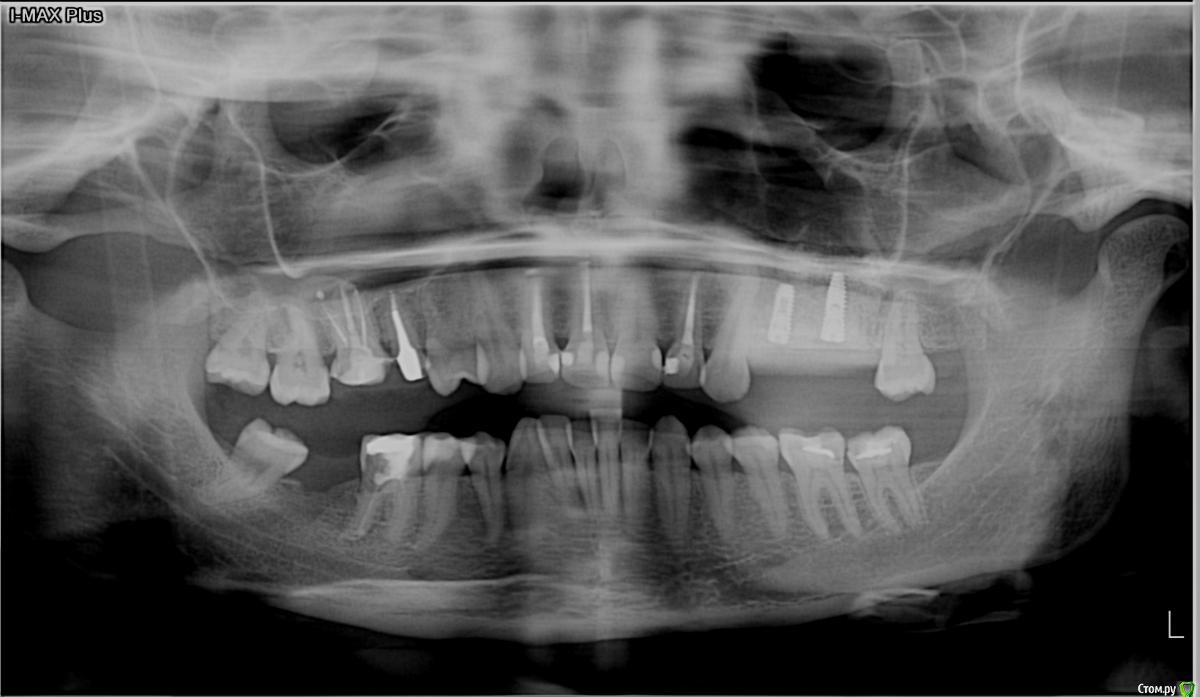

kamranchick Опубликовано 29 сентября, 2017 Поделиться Опубликовано 29 сентября, 2017 Господа, имеется проблема.Синус лифтинг с имплантацией произведено 7 сентябряНа этапе снятия швов все было хорошо.сегодня 29 сентября пациентка пришла с отеком, и говорит пару дней была температура... со стороны полости рта, гиперемия слизистой оболочки и боли в области проекции окнакакая тактика? Ссылка на комментарий